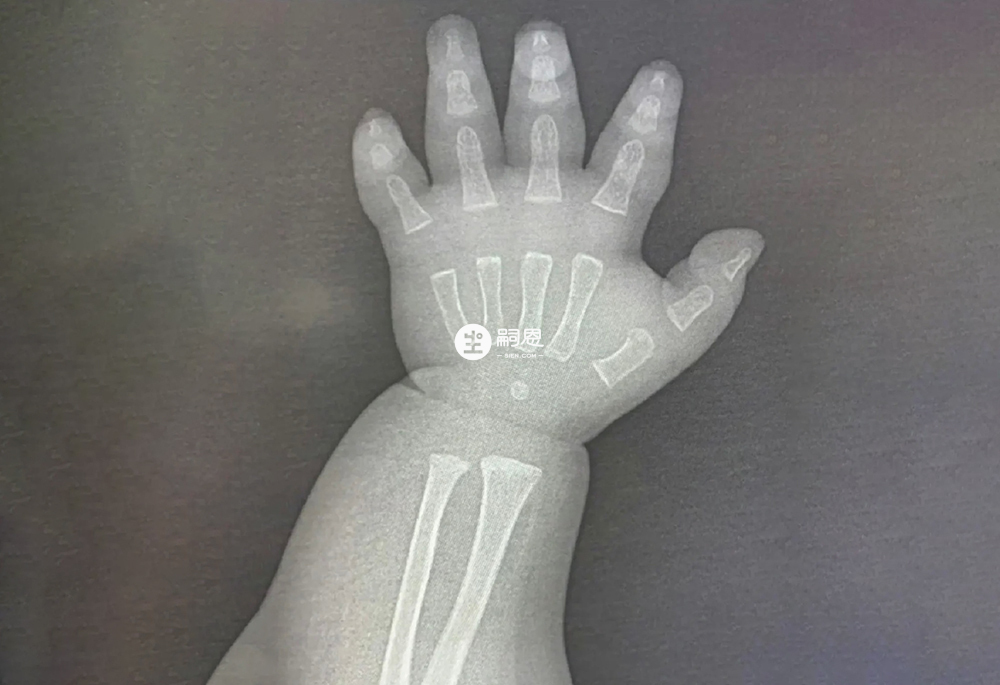

在出生時新生兒的骨骼處於不太成熟的階段,主要表現為骨組織低度礦化以及骨骼稚嫩。然而影響骨骼成熟度的發展因素有很多,比如:遺傳、營養、環境、生長激素以及活動程度等。一般來說在新生兒的第三個月時,其骨骼已經得到了發育,這一階段主要表現為骨量增加、礦物質含量提高、骨骼穩定性增強等等。要知道骨齡成熟速度通常為每年1歲,大致與生活年齡相當。但是骨骼的發育受到先天遺傳因素以及後天營養、運動、睡眠、心理等多種因素的影響,骨齡的成熟速度往往與年齡增長並不相符。由於不合理的餵養及生活習慣,往往會加快骨齡的成熟速度,導致骨齡超前,大於實際年齡。接下來我們來具體說下寶寶在骨骼發育期,家長經常踩的三個雷區。

剛開始學走路的寶寶搖搖晃晃,長輩們擔心寶寶摔倒所以習慣性的牽著寶寶的手走路,千萬別這麼做,嬰幼兒骨骼硬度差、彈性大。尤其兩歲以下孩子剛學會走路,家長長時間單側向上牽領走,孩子重心易發生偏移,這對骨骼發育不利如若寶寶不小心跌到,會有脫臼的可能